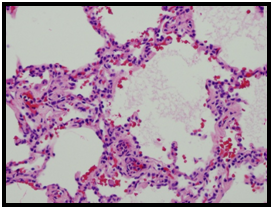

Figure 6 Histopathology-low power.

Figure 7 Histopathology-high power.

Histopathologic diagnosis of the RML lobectomy and supplying bronchus resulted pleuropulmonary blastoma, regressed type 1r. Given the rarity of this lesion (less than 400 cases identified), the entire case and pathologic specimens were sent and gained diagnostic agreement with the international pleuropulmonary blastoma registry in Minnesota, USA.